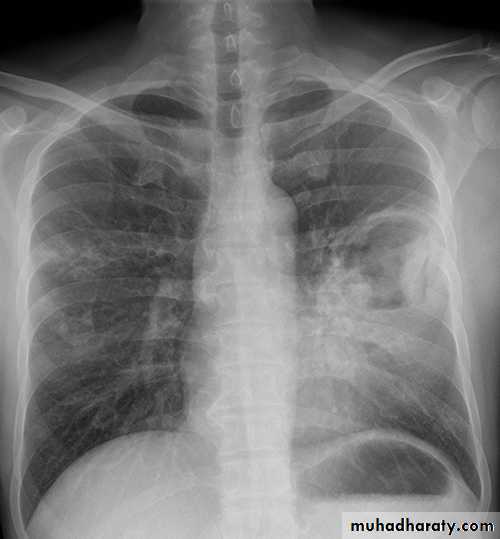

(a) Chest x-ray and (b) CT scan from a 27-year-old student with disseminated tuberculosis . Multiple small opacities (miliary shadowing) are seen in the periphery of the chest x-ray and much more clearly in all areas of the CT scan

Auscultation of the chest is frequently normal, advanced disease crackles .

Fundoscopy show choroidal tubercles.The classical appearances on chest X-ray are of fine 1-2 mm lesions ('millet seed').